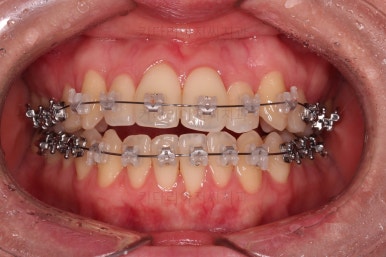

1년 2개월이라는 비교적 짧은 기간안에 원하시는 부분을 깔끔하게 개선했습니다.

전후 비교해 볼게요.

이번 환자분도 삐뚤한 치열을 비발치로,심지어 미니스크류 사용도 없었고 치간삭제도 거의 하지 않았는데요.

입이 나오거나 뻐뜨러지는 느낌 전혀 없죠?

진료 메카니즘을 잘 구성하고 철사를 잘 다뤄주면 좋은 결과를 얻을 수 있답니다.